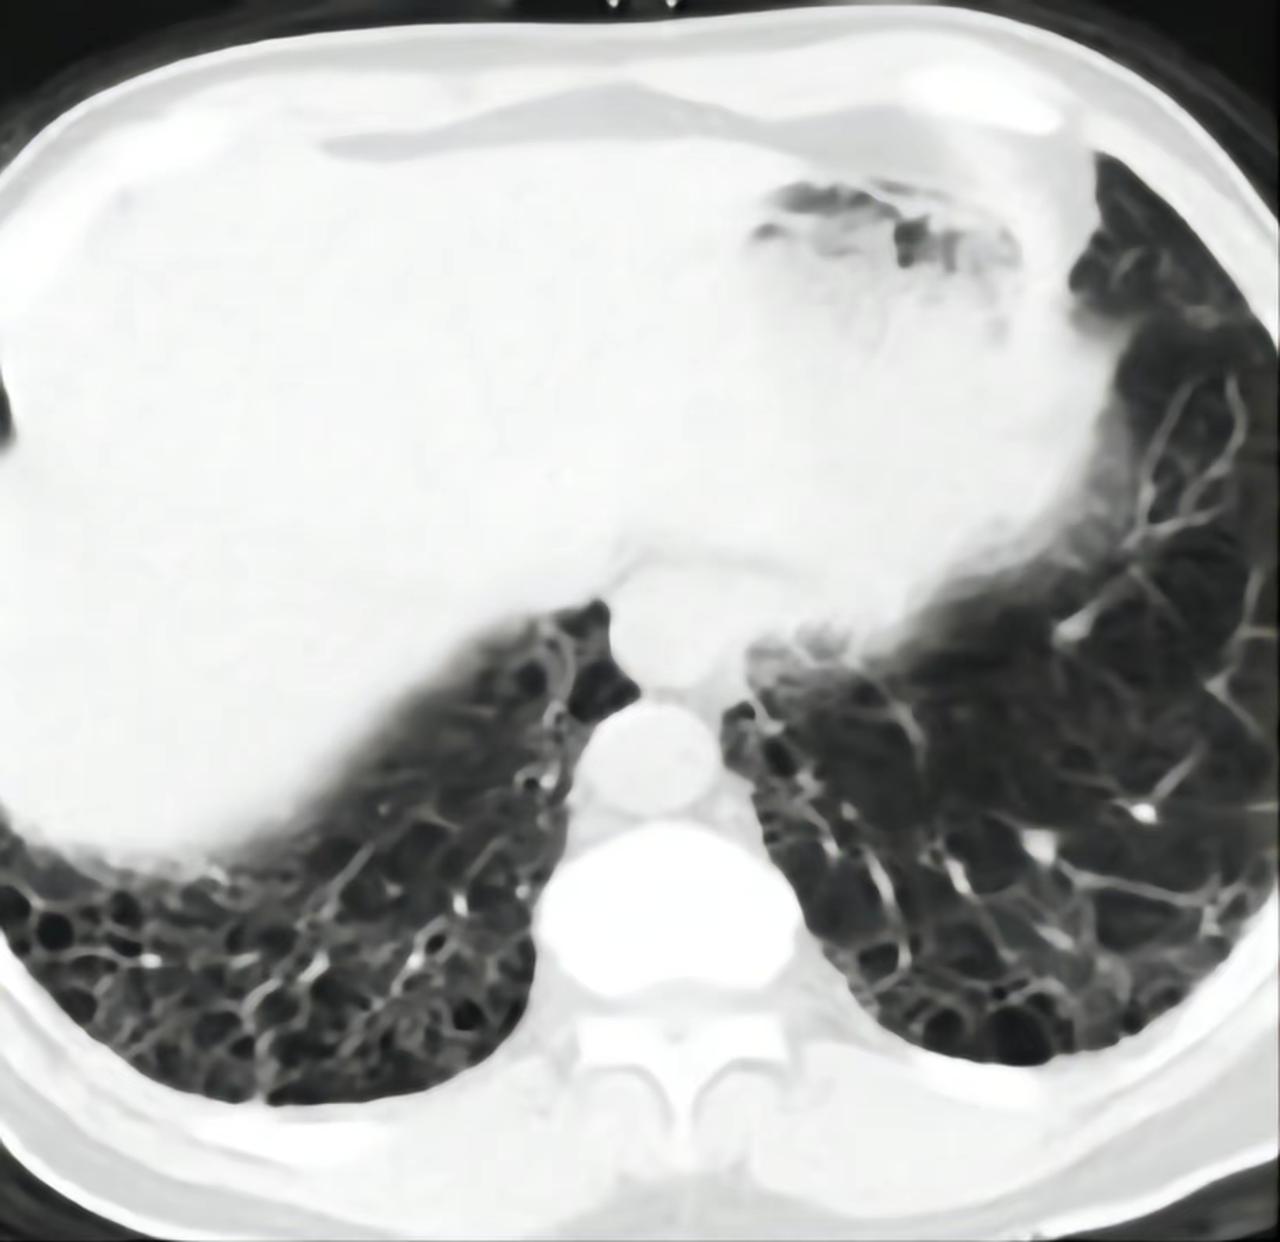

肺CT出现这4种情况都不需要药物干预。1、肺大泡 属于局限性肺气肿,一般只需注意